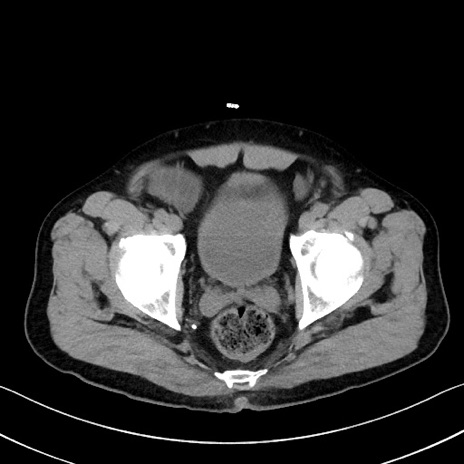

症例35(横断像)

【症例】70歳代 男性

【主訴】腹部膨満、嘔吐

【現病歴】昨日より腹部膨満感出現。本日増悪し、仙痛出現。嘔吐あり、受診。

【既往歴】糖尿病、胆摘後

【身体所見】BP 149/80mmHg、HR 74/min、BT 35.9℃、腹部:膨満、軟、圧痛なし。腸雑音減弱あり。上腹部正中切開瘢痕あり。

【データ】WBC 13500、CRP 1.72